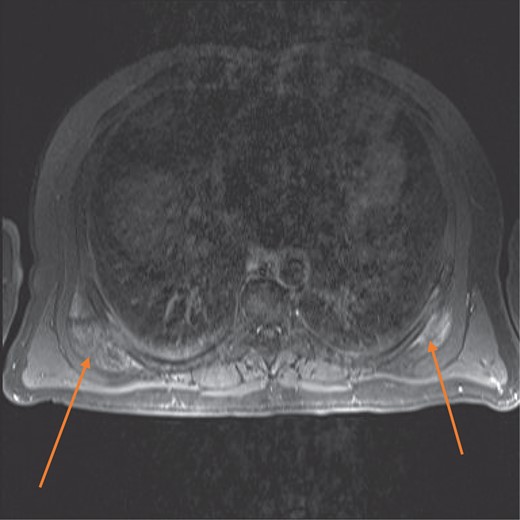

MRI confirmed the diagnosis and showed a second lesion on his left side, also at the infrascapular area (Figs 1–3). The patient had not complained of any symptoms to his left side or his left shoulder joint. After an extensive discussion with the patient and his family, we decided on a computerized tomography (CT) guided true cut biopsy to confirm the diagnosis (Fig. 4).

MRI axial view showing bilateral elasto fibromas (orange arrows) on the posterior rib cage.